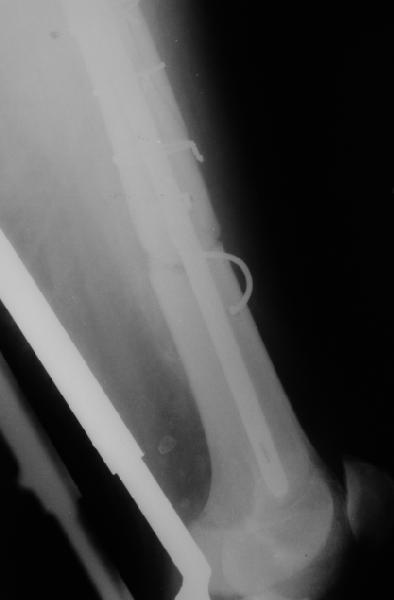

Уважаемые коллеги,пожалуйста, подумайте над следующим ребусом. В нашу клинику поступилпациент из области, 17лет, получивший травму в ДТП 25.08.04, открытый перелом бедра, при поступлении наложено скелетное вытяжение.

30.09.04 на операции выявлен вывих бедра и перелом голени на этой же стороне. Остесинтез бедра все же выполнен, и по заживлении раны пациент переведен к нам. Кроме того у пациента нейропатия седалищного нерва на этой же стороне. В нашей клинике планируется наложение аппарата таз-бедро, для постепенного низведения бедра с последующим открытым вправлением, замена фиксатора на запираемый гвоздь и блокируемый остесинтез голени. Вариант с первичным эндопротезированием мы не рассматривали из-за юного возраста пациента. Вопрос с чего начать? Кроме того, сгибание в коленном суставе в настоящее время (95 градусов) затрудняет остеосинтез голени.Стоит-ли менять гвоздь? Или же спилить торчащий конец во время открытого вправления? Может, попробовать все сделать одномоментно? Заранее спасибо.

Просьба простить за длительное молчание, не было фотоаппарата, чтобы перенести рентгенограммы. Больного прооперировали в прошлый четверг, как и предполагали, голень проблем не доставила(настолько, что даже не ввели дистальные винты по ряду причин: срок после травмы, целая малоберцовая, последующая длительная ходьба без нагрузки, да и гвоздь сел плотно). Изначально планировали после удаления фиксатора антеградно завести стержень и утопить конец, но вопрос был исчерпан, когда выяснилось, что все имеющиеся стержни слишком длинные, пришлось ретроградно забить большеберцовый гвоздь, после рассверливания; серьезные проблемы возникли с устранением ротации. В вертельной области сломали стержень-джойстик(привет установщику эндопротеза), дальнейшие манипуляции проводили пучком спиц и стержнем с кондуктором. Закончили все аппаратом таз-бедро. Решили что возможные огрехи с ротацией устраним после открытого вправления. Снимки прилагаю. Спасибо за участие в обсуждении. Обязуюсь информировать о дальнейших этапах лечения.